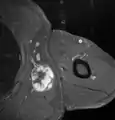

Fig. 7 MRI of myxoid liposarcoma of high grade, in the left axillary region of 40-year-old man, highlighted by its white color, in this horizontal section of the tumor.